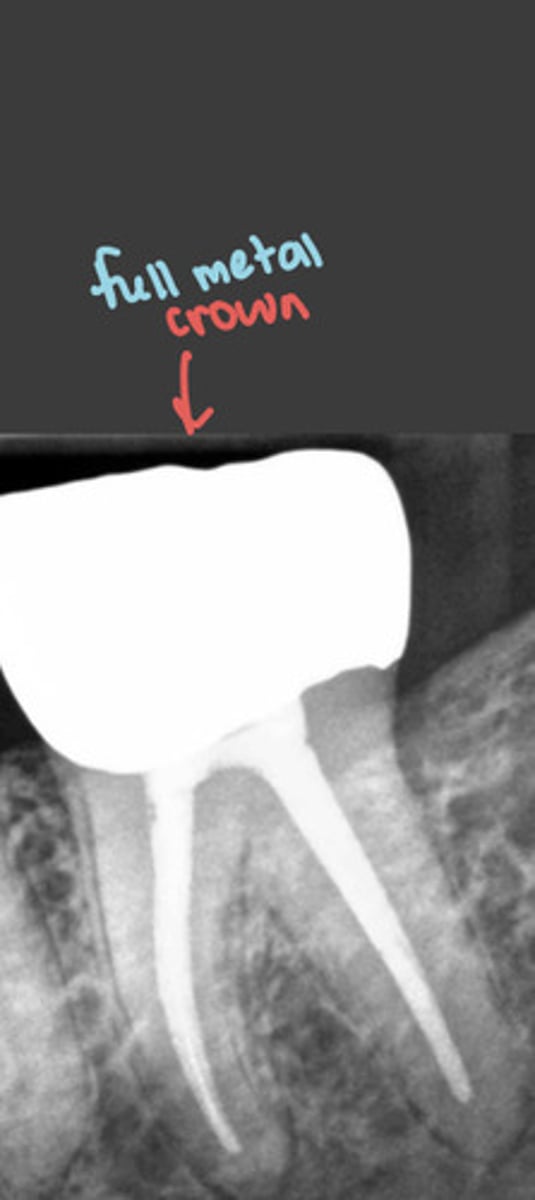

full metal crowns